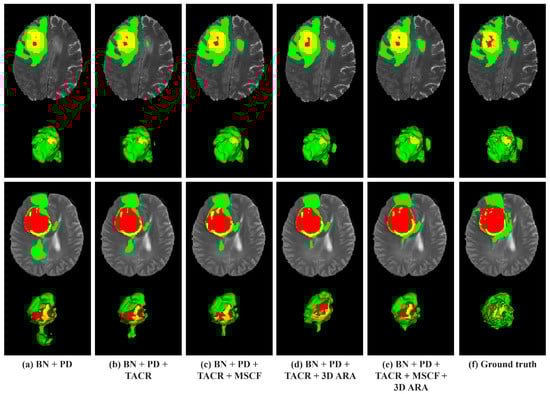

4.5.2. Assessment of Impact of Proposed Modules

In the second ablation study, meticulous evaluations were performed to discern the individual contributions of each component module to the overall performance of the proposed model. This comparative analysis involved the base network (BN), which comprised a CNN encoder and a PD, as well as variations in the base model enhanced with additional modules: the TACR, MSCF, and 3D ARA modules. These modules were methodically integrated to examine their individual and collective impacts on segmentation accuracy. The results are presented in Table 4, with the best performances highlighted in bold.

In our experiments on the BraTS 2020 dataset, the introduction of our designed modules led to notable improvements in the segmentation performance compared to the BN. Specifically, the Dice scores increased by 1.05%, 1.27%, and 3.09% for the ET, WT, and TC tumor regions, respectively. Moreover, the Hausdorff Distances showed significant reductions of 5.791 mm, 3.11 mm, and 15.925 mm across these regions. These enhancements attest to the effectiveness of our modules in brain tumor segmentation tasks. The implementation of the TACR module led to improved performance in all tumor regions, both in terms of Dice scores and Hausdorff Distances. This improvement can be attributed to TACR’s capability to handle unique 3D spatial orientations of MRI data (axial, coronal, and sagittal), enabling the model to accurately capture and emphasize critical features. Further integration of the MSCF module yielded higher Dice scores and lower Hausdorff Distances. This outcome demonstrates the capacity of the MSCF module to reflect the complexity and variability of tumor sizes and their spatial distribution within the MRI data. When the 3D ARA module was added, without the MSCF module, there was a slight decrease in Dice scores compared to configurations using the MSCF module. However, the 3D ARA module’s focus on capturing essential details for accurate tumor boundary delineation resulted in improved accuracy in terms of Hausdorff Distances. This highlights the importance of high-resolution feature capture for enhancing segmentation precision. Ultimately, integrating all modules resulted in the highest segmentation accuracy, confirming the synergistic benefits of our comprehensive module design.

Figure 8 presents visualization results of the ablation study for the configuration modules on the BraTS 2020 dataset. From left to right, each column represents the base model, the model incorporating the TACR module, the model introducing both the TACR and MSCF modules, the model introducing both the TACR and 3D ARA modules, the model with all the modules integrated, and ground truth. In the visualization results, the performance in the ED region, marked in green, was inaccurately predicted across all models, excluding the model incorporating all modules. Specifically, in the first row, there was a failure to predict the ED region located on the right side, which aligned with the ground truth. Conversely, in the second row, normal tissue was erroneously identified as the ED region.

Figure 8.

Visual comparison of tumor segmentation outputs from different configurations of the proposed model on the BraTS 2020 dataset. The colors indicate regions of tumors. Red: NCR/NET; yellow: ET; green: ED.